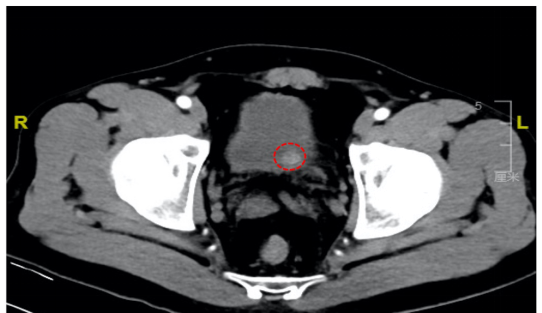

进一步CT检查显示在膀胱肌层内一直径约2cm球形高密度影。结合病史,几乎可以确诊膀胱内的肿块就是异位的“嗜铬细胞瘤”(又称“副神经节瘤”),在肾上腺相关生化激素指标检查后,阿辉体内的定时“炸弹”找到了。它大量产生的儿茶酚胺,可能正是“升压激素”,这就是阿辉出现尿晕的“元凶”。

盆腔CT显示,阿辉膀胱壁有高密度肿块